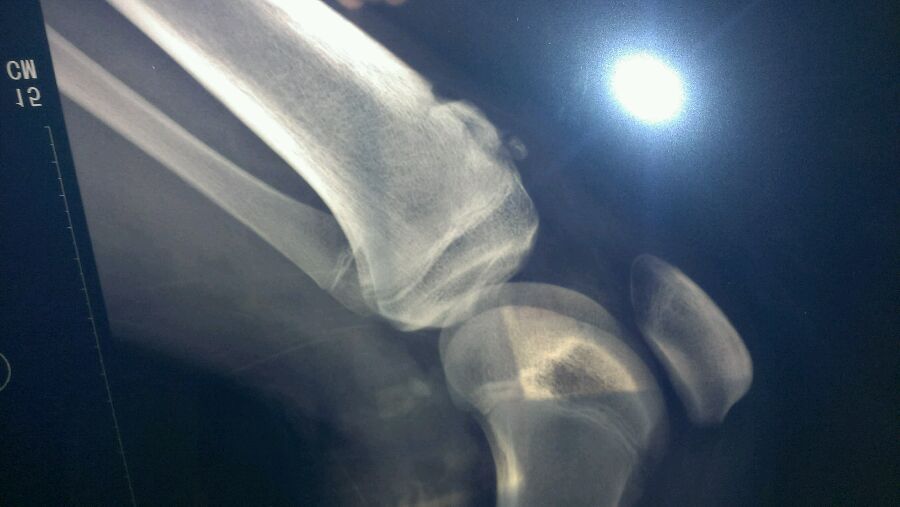

这这这………是膝盖骨移位了?

不是,我好像片子拍反了,反正就是膝盖以下凸起

股骨骨折

股骨下端那里骨质断出来了,具体不知道怎么治,还是去医院吧

楼主几岁?这是骨垢炎吗

是不是膝盖下方有一块骨头突出 碰一碰还会痛?

这是骨垢炎 大家别瞎猜了

胫骨结节骨骺炎,青少年常见,会自愈的